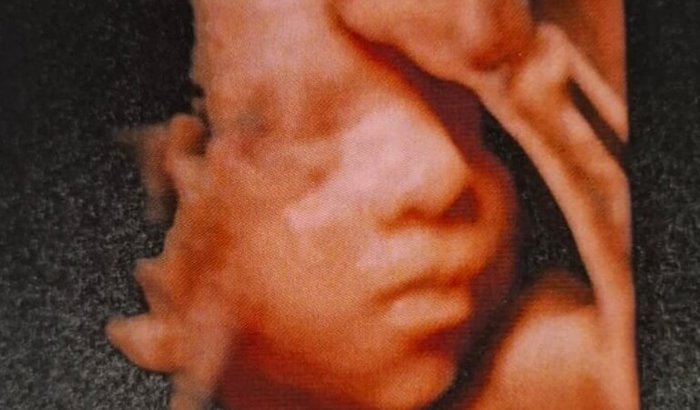

Ainda na barriga, nosso filho Frederico recebeu um diagnóstico difícil: raquisquise, uma forma grave de mielomeningocele. As últimas cinco vértebras dele estavam abertas e expostas ao líquido amniótico, o que pode causar danos progressivos ao sistema nervoso. Com a abertura, houve perda de pressão e o cérebro dele acabou deslocado.